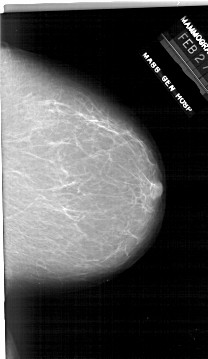

A_1916_1.RIGHT_MLO

RIGHT_MLO LINES 6286 PIXELS_PER_LINE 3721 BITS_PER_PIXEL 12 RESOLUTION 43.5 NON_OVERLAY